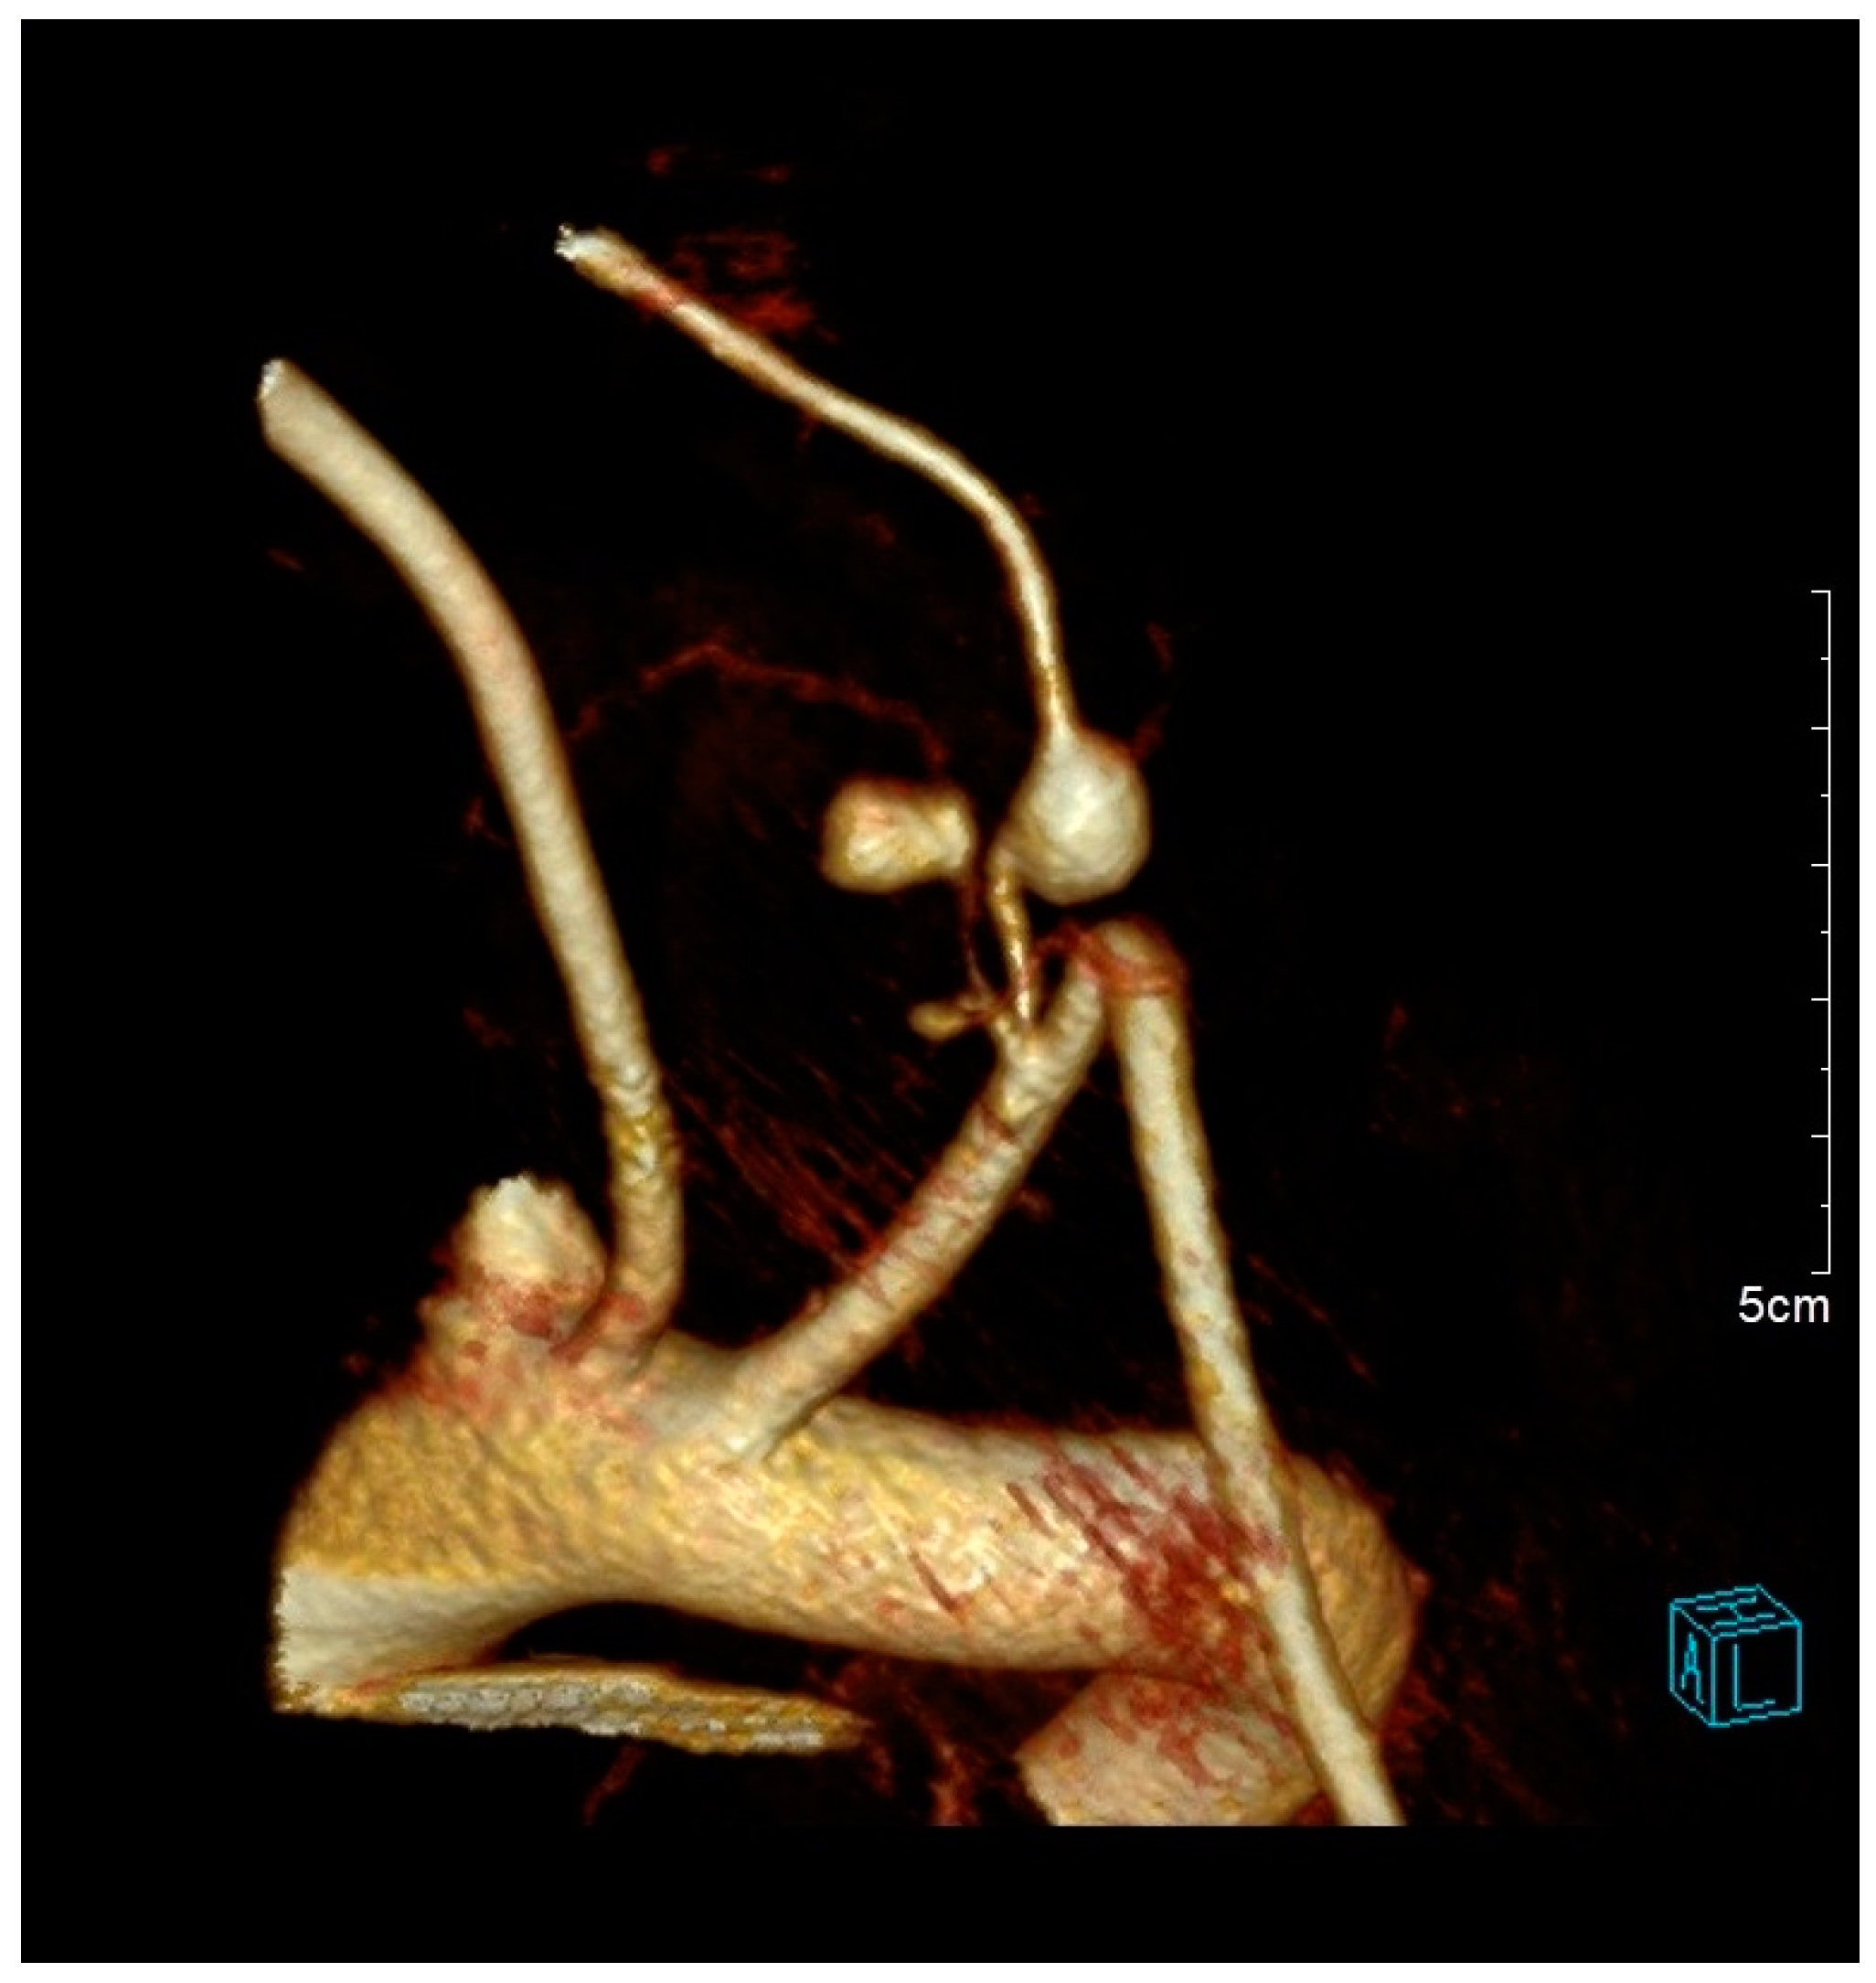

Successful Management of Thyrocervical Trunk Aneurysm Ruptured into the Thoracic Cavity After Cesarean Section in Nonstable Patient with Neurofibromatosis Type I

2. Case Description